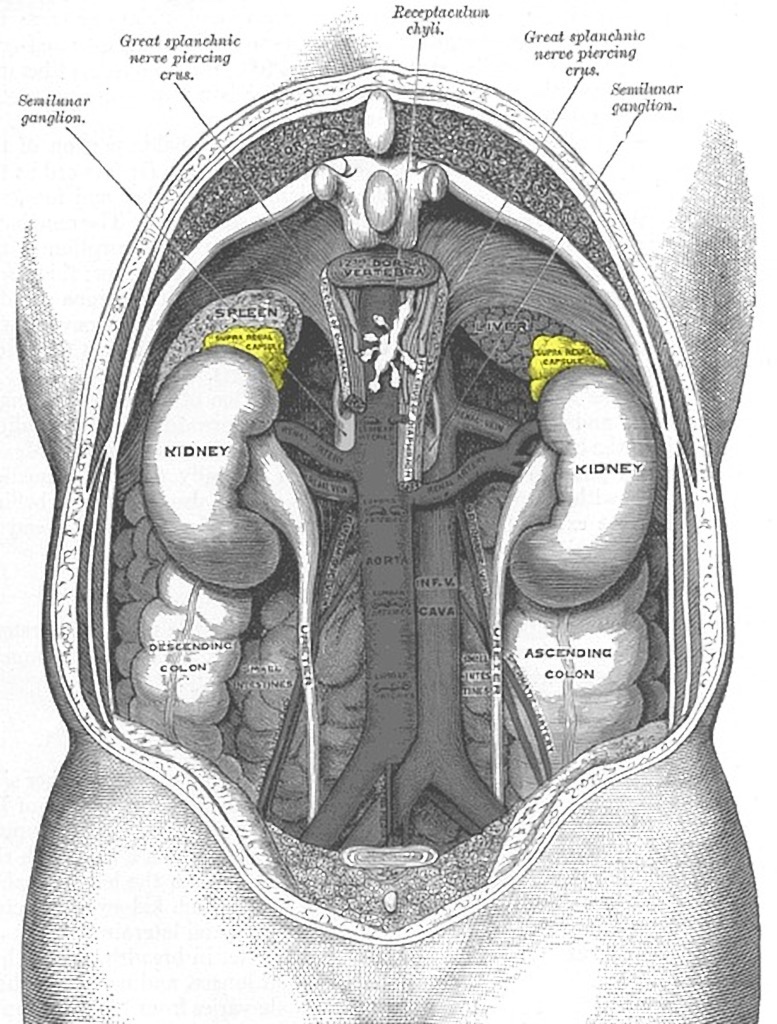

The tumors arise from the neural crest cells of the sympathetic nervous system.

The most commonly occur in the abdomen (65%) followed by the chest, neck and pelvis.